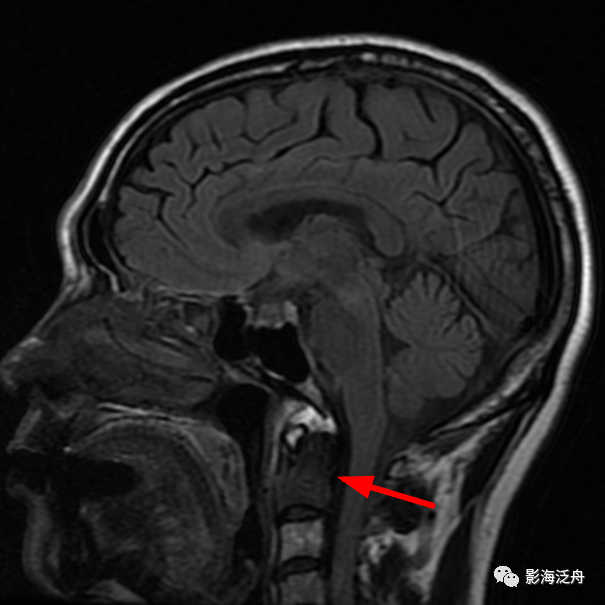

乳腺癌术后患者,枢椎骨质信号异常,随访证实为骨转移。随着肿瘤患者越来越多,行颅脑MR检查排除脑转移的检查也逐渐增多,不要只顾着在脑子里面找转移灶,周围的结构也应该观察一下。

矢状位上另一个需要观察的就是齿状突的高度,异常增高往往是颅底凹陷症导致的(红线为钱氏线)。